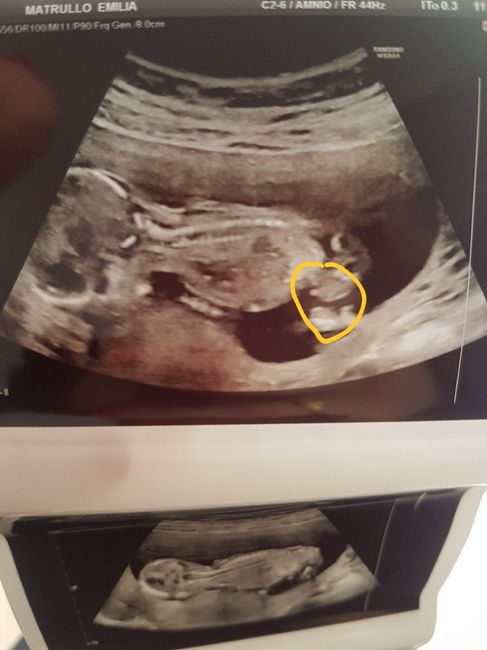

Buongiorno mammine.... vi presento il mio fagottino oggi ho saputo che è maschio ve lo ho evidenziato in giallo... Non so xke ma nn mi sembra che è maschio mi sento una femminuccia... mi sembra che in questa eco fosse un piedino voi ch3 ne pensate......